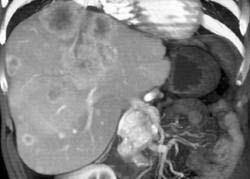

男,48岁,胃癌术后1年,未化疗,CT检查如图所示,最可能诊断为 ( )A.肝癌B.肝转移癌C.肝血管瘤D.肝脓肿E.肝囊肿

问题 男,48岁,胃癌术后1年,未化疗,CT检查如图所示,最可能诊断为 ( )

选项 A.肝癌 B.肝转移癌 C.肝血管瘤 D.肝脓肿 E.肝囊肿

答案 B